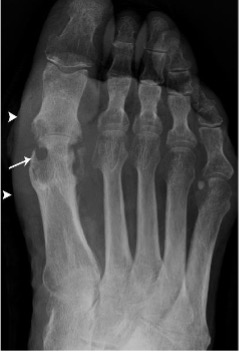

Gout

- Hyperuricaemia causes deposition of urate crystals

- First metatarso-phalangeal joint is commonly involved, termed a podagra

- Well-defined erosions with sclerotic borders which have a ‘punched out’ or ‘rat bite’ appearance and overhanging margin

- Joint space and bone density are preserved until late in the course of the disease

- Urate crystals deposited in the soft tissues form tophi and periarticular lobulated soft tissue masses

Gout of first MTP joint with well defined ‘punched out’ erosion with overhanging margin (arrow) and soft tissue swelling (arrowheads)